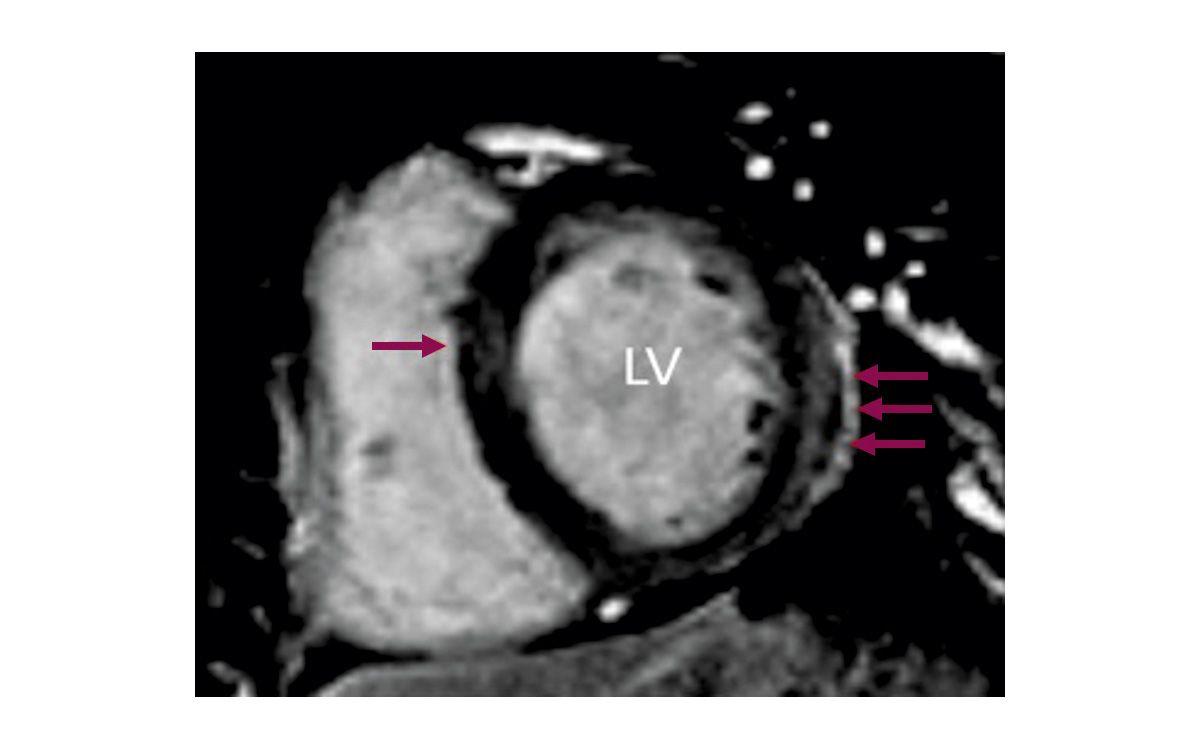

Das kardiale MRT bietet eine besonders präzise Quantifizierung von Hypertrophie, Funktionsparametern und Gewebecharakterisierung [11]. Es kann insbesondere bei schwereren Formen der kardialen Beteiligung mittels Late Gadolinium Enhancement (LGE) helfen, das Ausmaß der Myokardfibrose zu ermitteln.

Fibrotisches Gewebe zeigt eine verzögerte Kontrastmittel-Rückbildung und erscheint als hell aufleuchtende Areale im MRT. Typischerweise findet sich bei Personen mit FA eine fleckige, unregelmäßige Fibrose, vor allem im linksventrikulären Septum und an der posterolateralen Wand (Abb. 4) [11].

Im Endstadium weisen nahezu alle Betroffenen ausgedehnte Myokardfibrosen auf, die mit einer deutlichen Einschränkung der Herzfunktion einhergehen [11, 20].

Ein Adenosin-Stress-MRT kann zusätzlich zur Beurteilung der myokardialen Perfusionsreserve eingesetzt werden. Unter Adenosin-Stimulation – die eine erhöhte Koronardurchblutung provoziert – zeigt sich bei vielen FA-Betroffenen eine verminderte Perfusionsreserve, oft bereits vor dem Auftreten klinischer Symptome [16, 22].